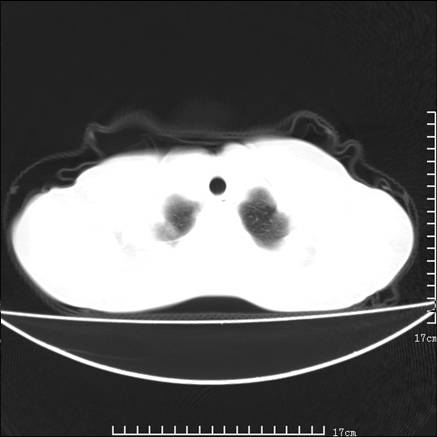

女,46岁,患胃溃疡多年,溃疡大小约1.0cm左右,后于5年前手术,病理为胃癌。主诉:半月前感冒后胸闷,气短,有咳嗽,无明显咳痰,无发热。偶有腰背部不适。

以下为高分辨扫描图像

双肺小叶间增厚,双肺散布粟米影和磨玻璃状影,以双肺上叶为重。结合病史考虑转移(癌性淋巴细管炎)可能性大。